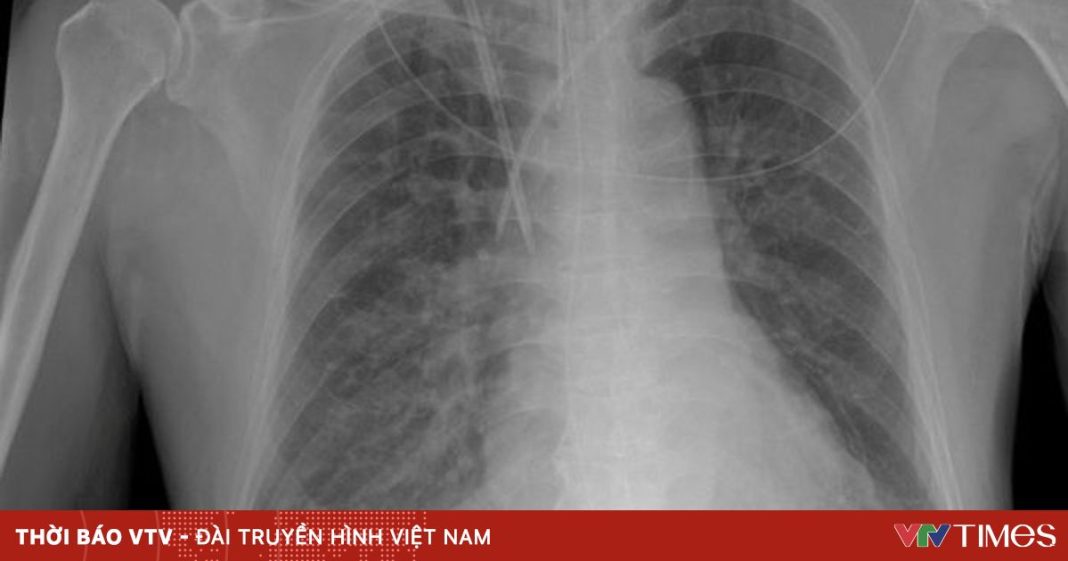

Cẩn trọng bệnh viêm phổi thùy ở trẻ trong thời tiết giao mùa Y tế 30/10/2025 Chia sẻ FacebookTwitterPinterestWhatsApp Cẩn trọng bệnh viêm phổi thùy ở trẻ trong thời tiết giao mùa Nguồn: VTV Chia sẻ FacebookTwitterPinterestWhatsApp PHIM ĐẶC SẮC TIN MỚI NHẬN Y tế Từ phản ánh của người dân đến đổi mới quản trị y tế tại TP Hồ Chí Minh Cao Quang Đại - 17/04/2026 Vòng quanh thế giới Lật tàu từ Bangladesh đi Malaysia, hơn 250 người mất tích Âu Thanh Tâm - 17/04/2026 Vòng quanh thế giới Thị trường vũ khí Nhật Bản sắp mở cửa lớn nhất sau Thế chiến 2 Âu Thanh Tâm - 17/04/2026 Món ngon Mang bánh tacos sang Việt Nam: Chàng trai Pháp làm chủ 5 tiệm, xem TP.HCM là nhà Âu Thanh Tâm - 17/04/2026 Vòng quanh thế giới Đã tìm thấy nhà của đại văn hào Shakespeare ở London Âu Thanh Tâm - 17/04/2026 Bóng đá Trong nước Techcombank và Hệ sinh thái đồng hành cùng VTV đưa FIFA World Cup 2026™ về Việt Nam Cao Quang Đại - 17/04/2026 Xe Sau 3 năm hoạt động, Xanh SM đổi tên thành Green SM Âu Thanh Tâm - 17/04/2026 Vòng quanh thế giới Phi công bị mắng vì giả tiếng mèo kêu với tháp không lưu Âu Thanh Tâm - 17/04/2026 Du lịch Những xu hướng du lịch nổi bật năm 2026 Cao Quang Đại - 17/04/2026 Bóng đá Trong nước Giải U.15 quốc gia có nhà vô địch mới, lần đầu bản lĩnh của U.15 Hà Nội Cao Quang Đại - 17/04/2026 Xe Hyundai nâng thời gian bảo hành vượt trội cho dòng xe Hyundai Solati Âu Thanh Tâm - 17/04/2026 TIN LIÊN QUAN Y tế Lạm dụng tai nghe và nguy cơ tổn thương thính lực 16/04/2026 Y tế Từ phản ánh của người dân đến đổi mới quản trị y tế tại TP Hồ Chí Minh 17/04/2026